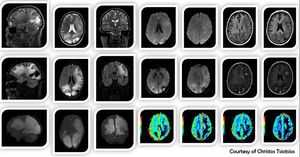

High-resolution, multiparametric (anatomical, functional  quantitative) MR Imaging of glioblastoma multiforme, based on volumetric acquisitions (3D T2, 3D T2 FLAIR, 3D T1 pre  post contrast, 3D SWI), SS-EPI DWI, DSC PWI and 3D MIP of the volumetric FLAIR for quantification purposes.